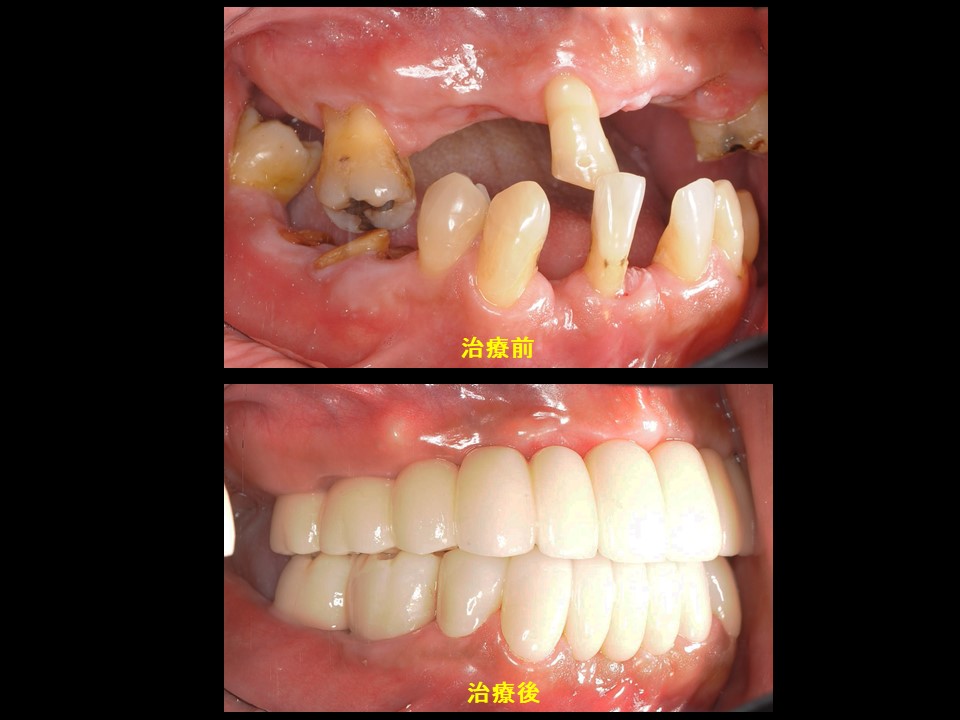

症例4